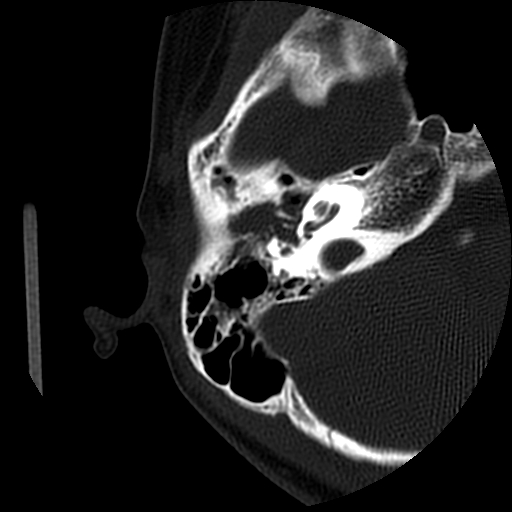

以下是引用随光逐影在2009-8-19 7:25:00的发言:[br]右侧慢性中耳乳突炎,右侧中耳腔及外耳道肉芽肿或胆脂瘤形成。